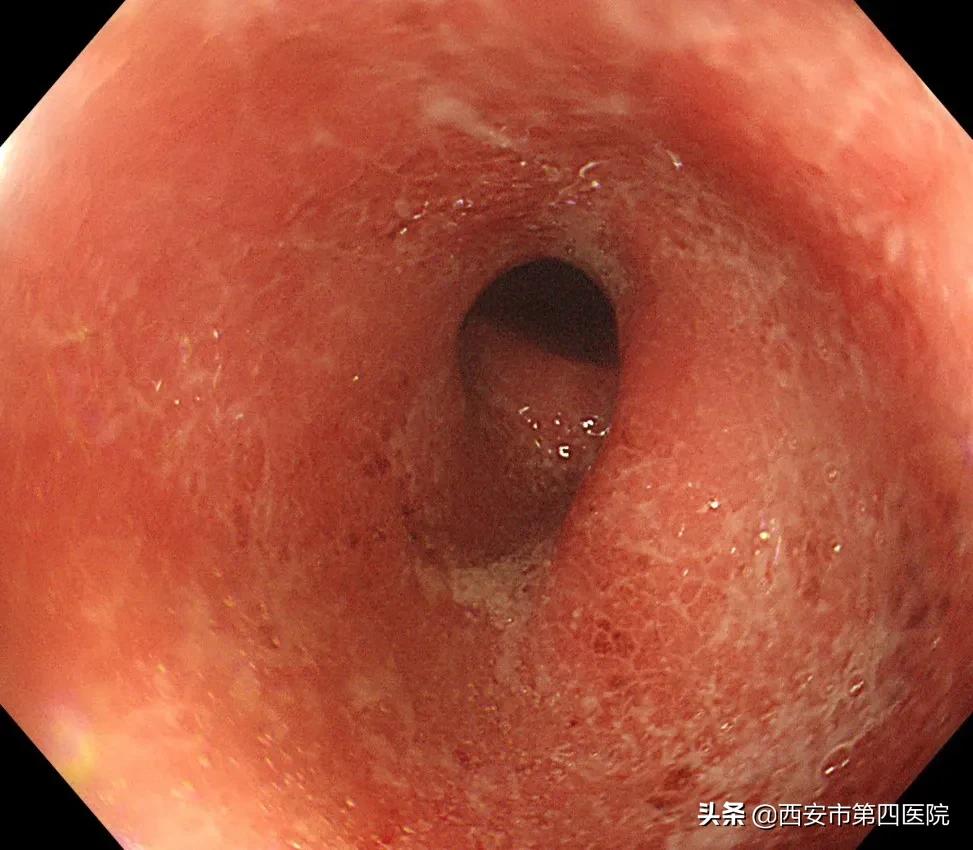

治疗前结肠镜图片

院内确定诊断为溃疡性结肠炎(慢性复发型、E3、重度、活动期),科室为患者制定了新的、个体化的治疗方案。经过主管医生郑君仪的精心治疗,患者腹痛、便血逐渐好转。10天后复查结肠镜提示肠道炎症及溃疡较前明显好转,大便约3次/日,无腹痛、无脓血便。

治疗10天后复查的结肠镜图片